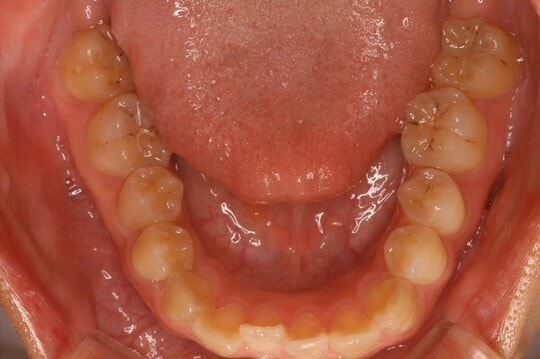

[図表2]は、Ⅱ型と分類しました。Ⅰ型に比べアーチの幅は狭く、V字形の歯並びをしています。歯が内側に倒れこんでいて、舌に歯の痕がついているのがおわかりいただけるでしょうか?

この歯の痕が「舌ストレス」で、現代人の典型的な形です。筆者のデータでは、70%の方がこれに属します。